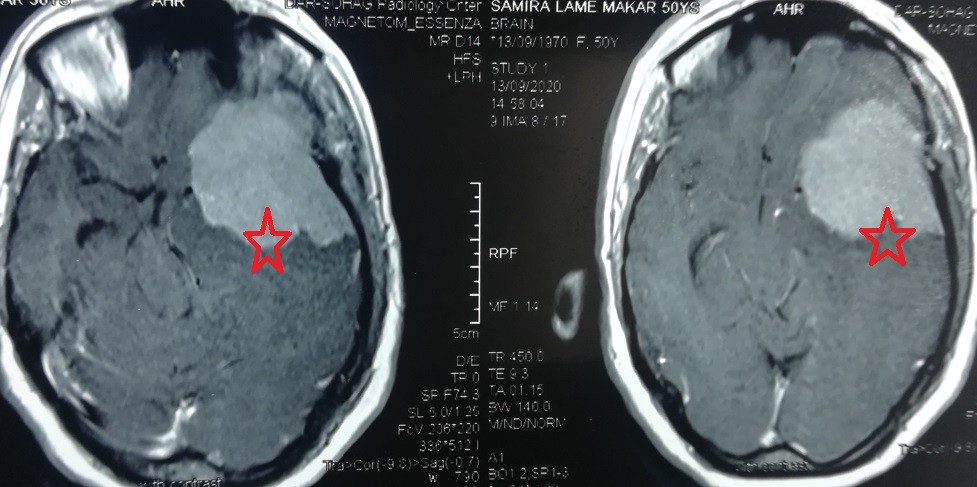

ورم سحائي ضخم بقاع الجمجمة بالجهة اليسري الصدغية

large meningioma at the base of the skull on the left temporal side

A huge meningioma at the base of the skull on the left side, extending into the temporal lobe and part of the frontal lobe, compressing the optic nerve, carotid artery, and left median artery. It clearly compresses all parts of the left hemisphere of the brain. It was completely removed without any significant brain problems, as shown by the radiographs in the follow-up four months after the surgery. The 50-year-old patient was suffering from persistent headaches, seizures and visual impairment. The patient is in very good condition and is going about her life as usual.